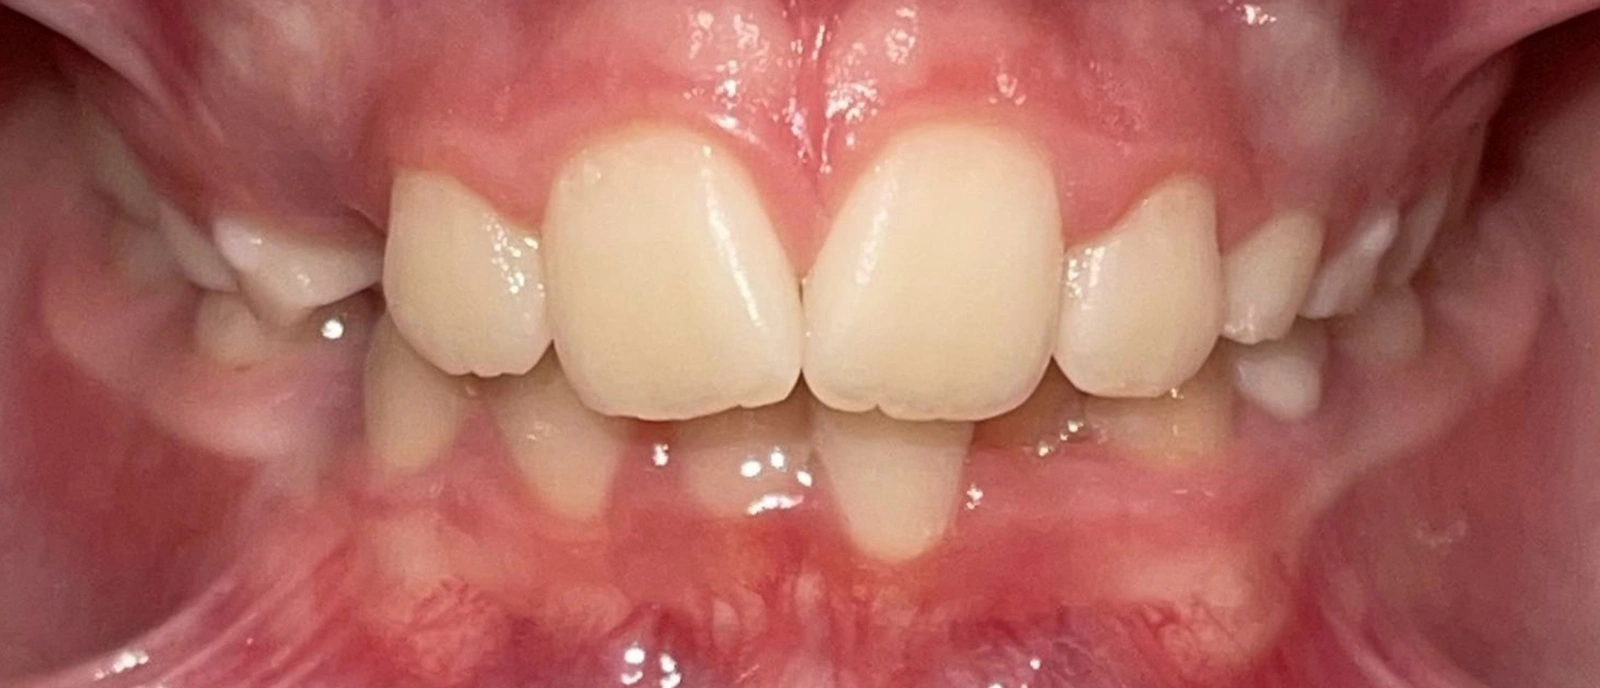

Actual Patient: Victoria

Img Before 1 1 Img After 1 1

Severe Crowding, Narrow Jaws, Severe Deep Bite

image 1 after img

8 months

Front View

Top View

Right & Left Sides